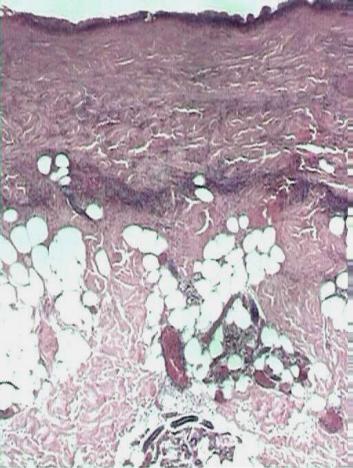

Рис. 70. Микропрепарат кожи при ожоге II степени:

над базальным слоем эпидер- миса полость (пузырь) (окраска гематоксилином и эо- зином, × 70)

Микроскопически обнаруживают (рис. 71), что вся толща эпидермиса и верхняя часть дермы некротизирована, а пузыри, в отличие от пузырей при ожогах II степени, образованы в результате отслоения всего пласта эпидермиса, включая базальный слой с его мембраной. В дне раны сохранены фрагменты волосяных фолликулов и сальных желез, потовые железы и участки их прото- ков. Возможны очаги кровоизлияний.

Рис. 71. Микропрепарате кожи при ожоге пламенем III «а» степени: коагуляционный некроз всей тол-

щи эпидермиса и верхней части дермы (окраска гематоксилином и эозином, × 70)